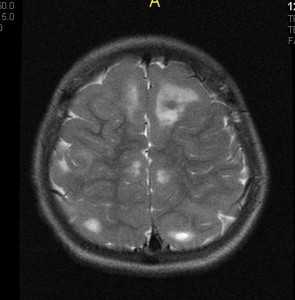

(а) МРТ, Т2-ВИ, аксиальный срез: у месячного ребенка определяются множественные гипоинтенсивные СЭУ, берущие начало от стенок боковых желудочков. Кора правой лобной доли утолщена и, вероятно, имеется ее диффузная дисплазия.

(б) Бесконтрастная КТ, аксиальный срез: у другого пациента определятся кальцификация СЭУ , расположенного вдоль передней границы преддверия левого бокового желудочка. Гиподенсная опухоль, вероятно, имеющая кистозную структуру, визуализируются в нижнем отделе левой лобной доли. (а) МРТ, FLAIR, аксиальный срез: у шестилетнего ребенка определяются множественные гиперденсные очаги линейной формы, имеющие нечеткие контуры, ориентированные радиально от коры к боковому желудочку.

(б) МРТ, Т1-ВИ с эффектом переноса намагниченности (МТ), аксиальный срез: у того же пациента определяются множественные гиперинтенсивные очаги, патогномоничные субкортикальным туберсам и радиальным линиям миграции в БВ. Оценка T1-ВИ с МТ позволяет поставить диагноз ТС намного легче и увереннее, чем при оценке FLAIR.

Что покажут снимки МРТ головного мозга при туберозном склерозе

- Обычно множественные

- Чаще всего встречаются в супратенториальном отделе

- У новорожденных они гиперинтенсивные по отношению к прилежащему, еще немиелинизированному белому веществу на Т1-ВИ и гипоинтенсивные на Т2-ВИ

- У детей постарше центр узлов выглядит гипоинтенсивным по отношению к белому веществу на Т1-ВИ и гиперинтенсивным на Т2-ВИ

- В зрелом мозге очаги могут быть изоинтенсивные на Т1-ВИ, но практически всегда гиперинтенсивные на Т2-ВИ

- Могут отмечаться кальцинаты

- FLAIR и метод переноса намагниченности дают больше диагностической информации относительно размера и количества очагов.